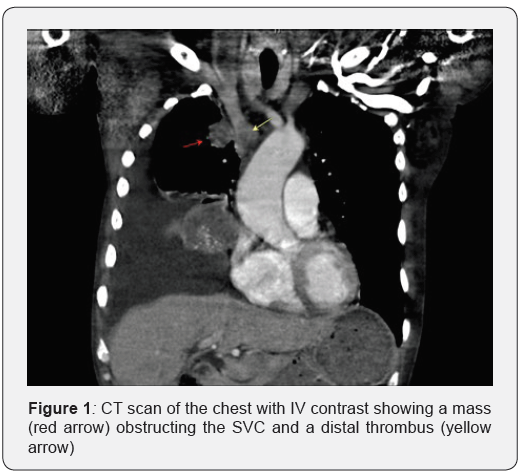

Prior to the biopsy the patient presented to the ED with dizziness and facial swelling for two weeks. He was hypotensive, tachycardic, and tachypneic with a large right pleural effusion on chest x ray. CT scan of the chest showed a lung mass partially compressing the superior vena cava at the area of its junction with the innominate vein with evidence of thrombosis distally (Figure 1). Therapeutic thoracentesis was performed alleviating the patient’s symptoms.